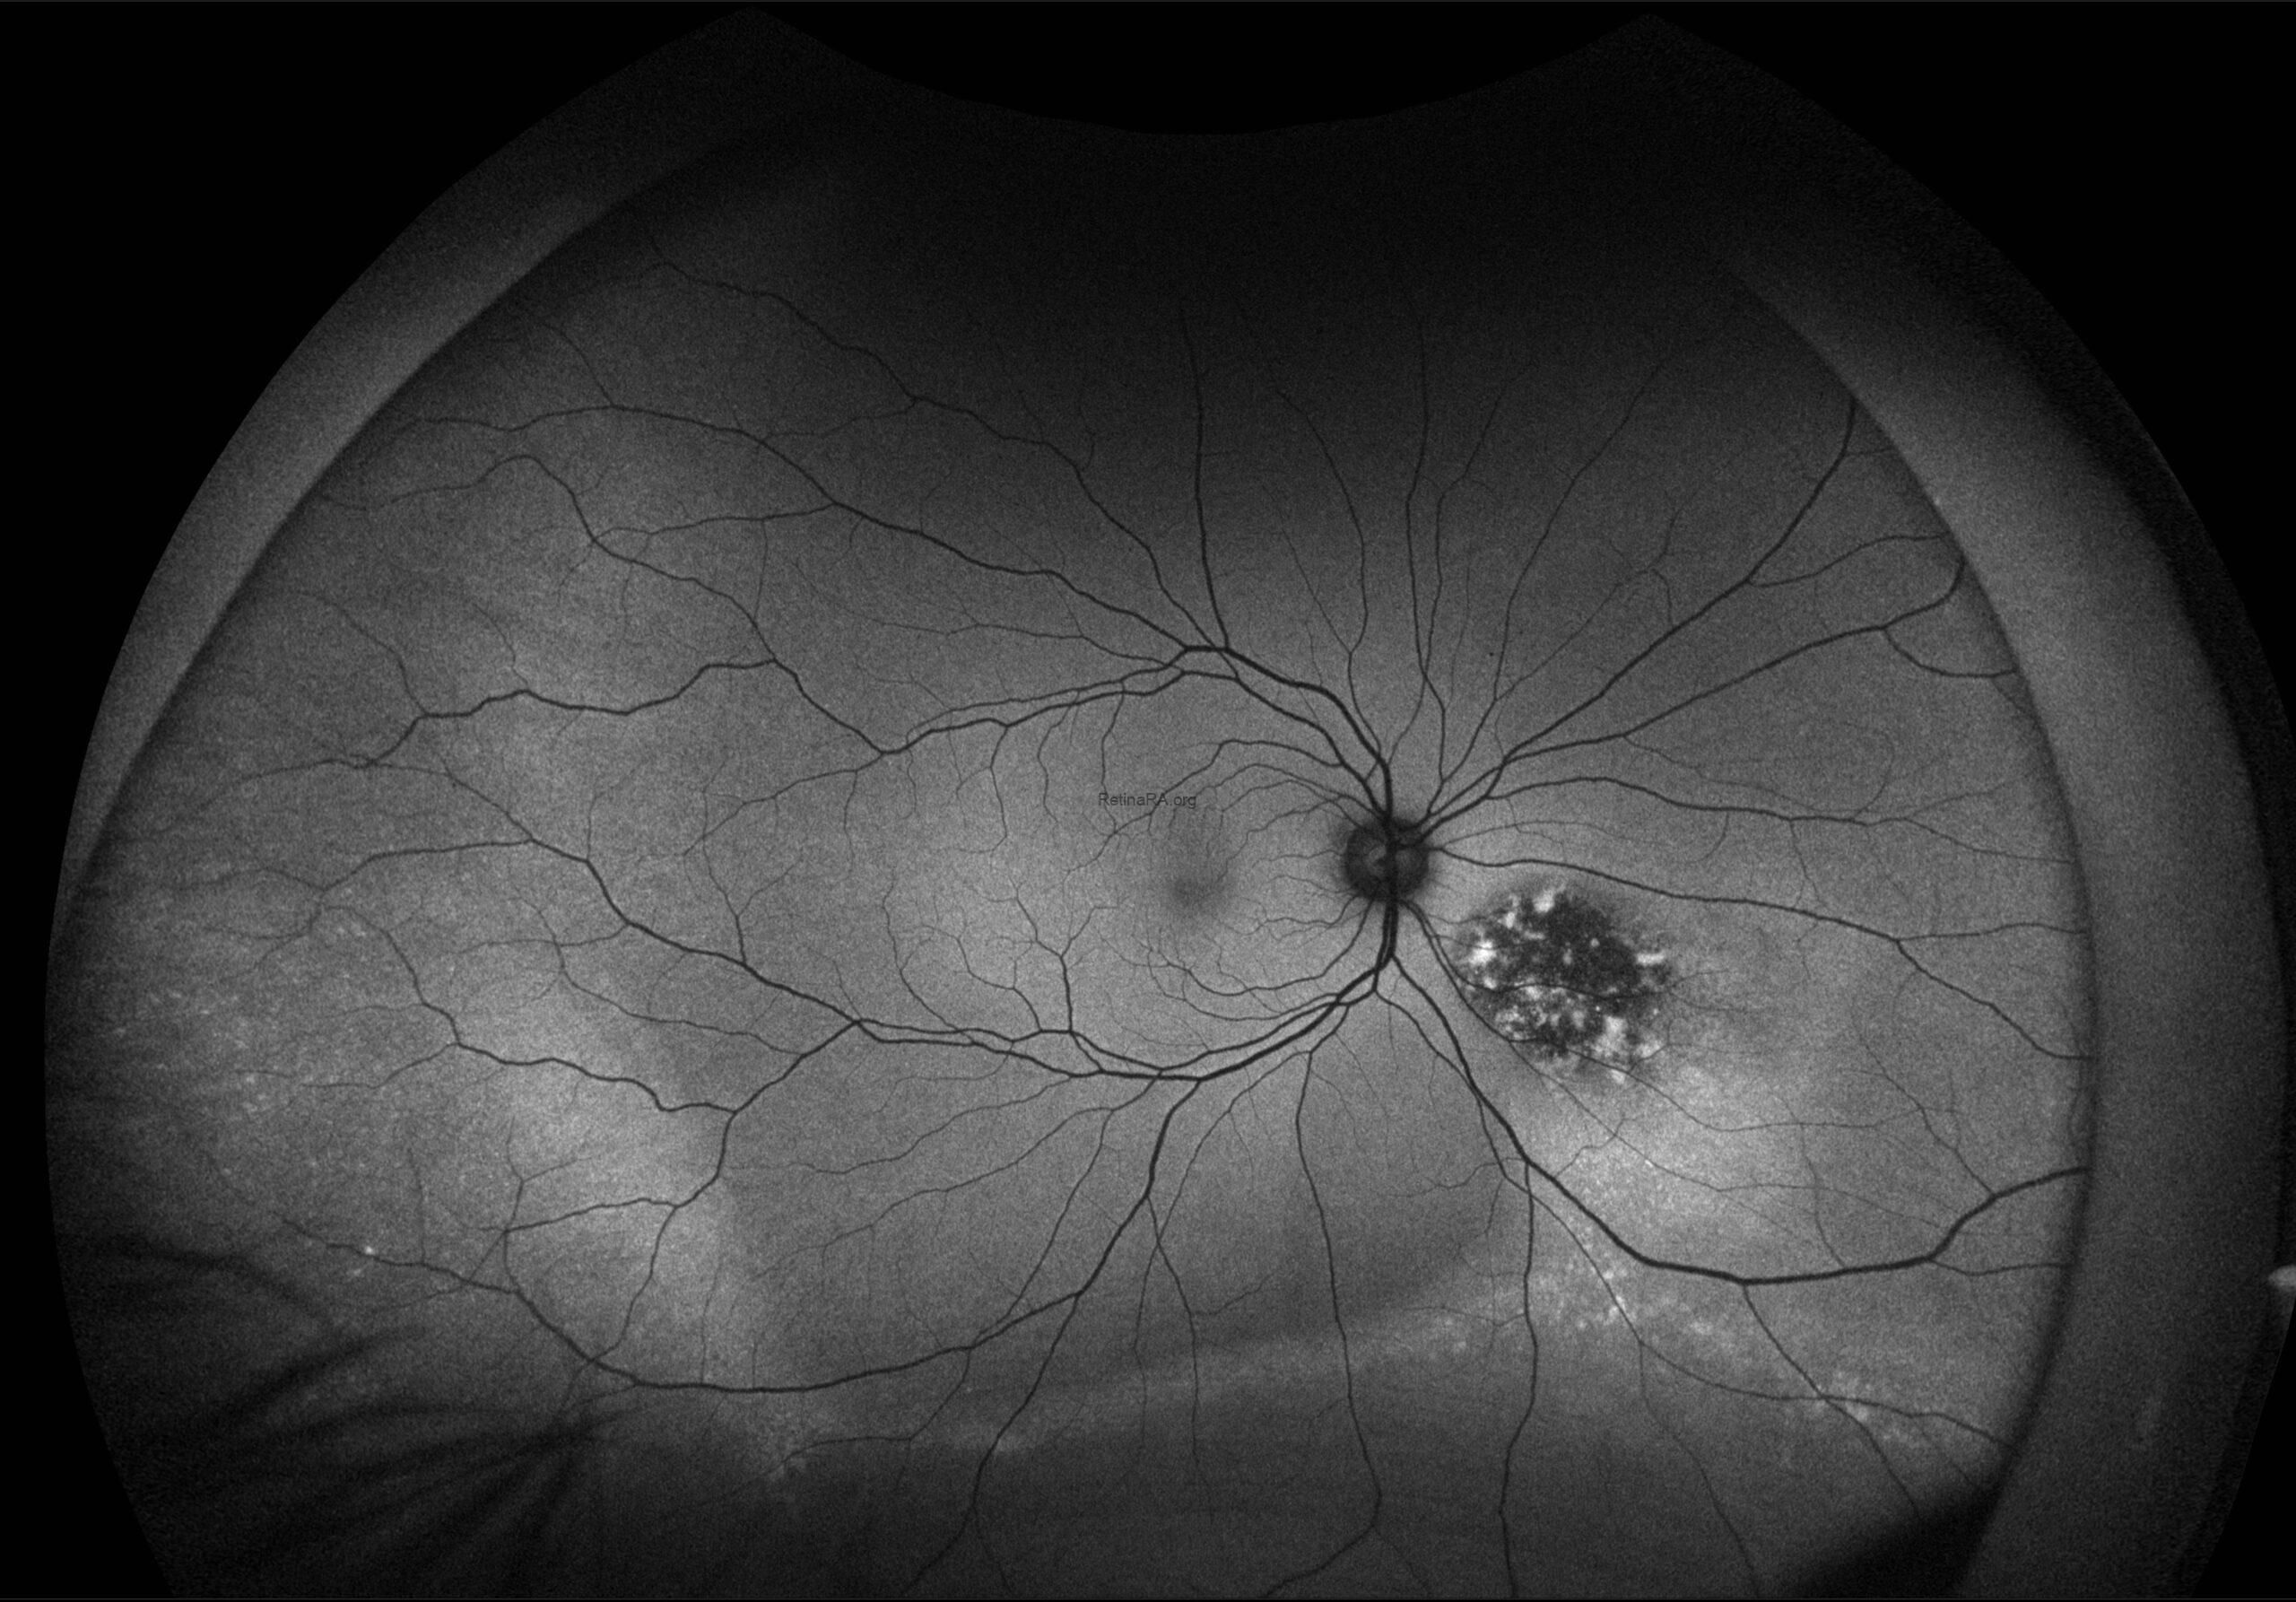

This FAF image reveals a hypoautofluorescent mass with areas of dense hyperautofluorescent stippling—a classic pattern suggestive of an amelanotic choroidal melanoma.

Clinically, the lesion appears as a dome-shaped, yellowish subretinal mass, often associated with subretinal fluid, lipofuscin deposition, or retinal detachment. The absence of pigment can delay diagnosis, making multimodal imaging essential.

Amelanotic melanoma is a rare variant of uveal melanoma, accounting for only a minority of cases. Unlike pigmented melanomas, these lesions lack melanin, making them more challenging to detect on conventional color fundus imaging.